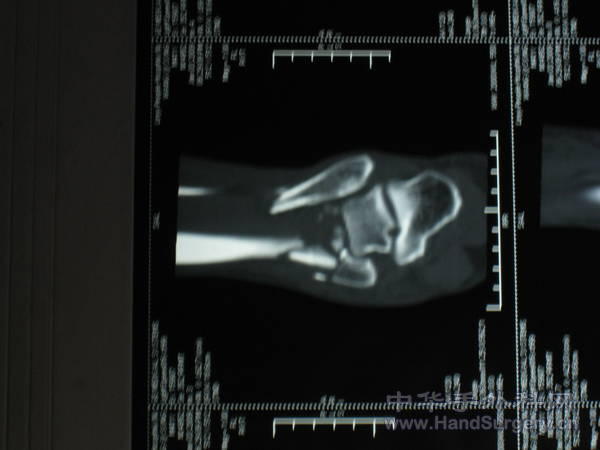

pilon骨折一例-手足外科魏宝富主任作品

pilon骨折在哪做都是高难度手术,骨性支架的建立应该最重要,皮肤缺损对手足外科大夫来讲已经不是什么难题 ,希望看到踝关节关节面的x线或ct。

魏主任:你的手术做的很好,但是不知关节面是如何处理的,植骨了吗?是急症做的还是消肿以后做的?切口愈合如何?还有外侧的关节面好像没有处理?

希望能看到术后CT片,了解关节面的情况。个人愚见,这种情况用外架固定是否更合理?